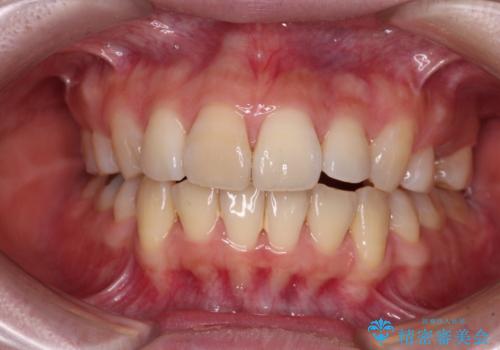

前歯のガタつきを改善 抜歯矯正後の後戻り

前歯を後ろに下げたい ワイヤー矯正(クリア装置)